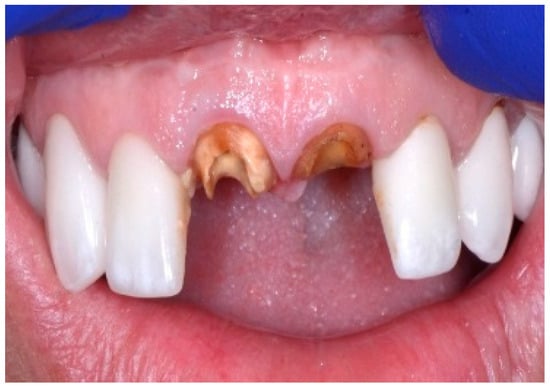

A 43-year-old female patient in good health and a non-smoker presented with a history of endodontic failure of the maxillary central incisors. She was interested in the replacement of her teeth with endosseous implants. The teeth had previously been treated endodontically with no lesion regression. Endodontic surgery had also failed. Clinical examination revealed class 1 mobility and a scar on the soft tissue above the maxillary anterior teeth. Radiographic examinations revealed the presence of chronic periapical lesions associated with teeth number 8 and 9, and clinically there was minimal remaining tooth structure (Figure 1). A treatment plan involving the placement of two immediate implants followed by future ceramic crowns was presented and accepted by the patient.

Figure 1.

Clinical view of existing maxillary incisors.